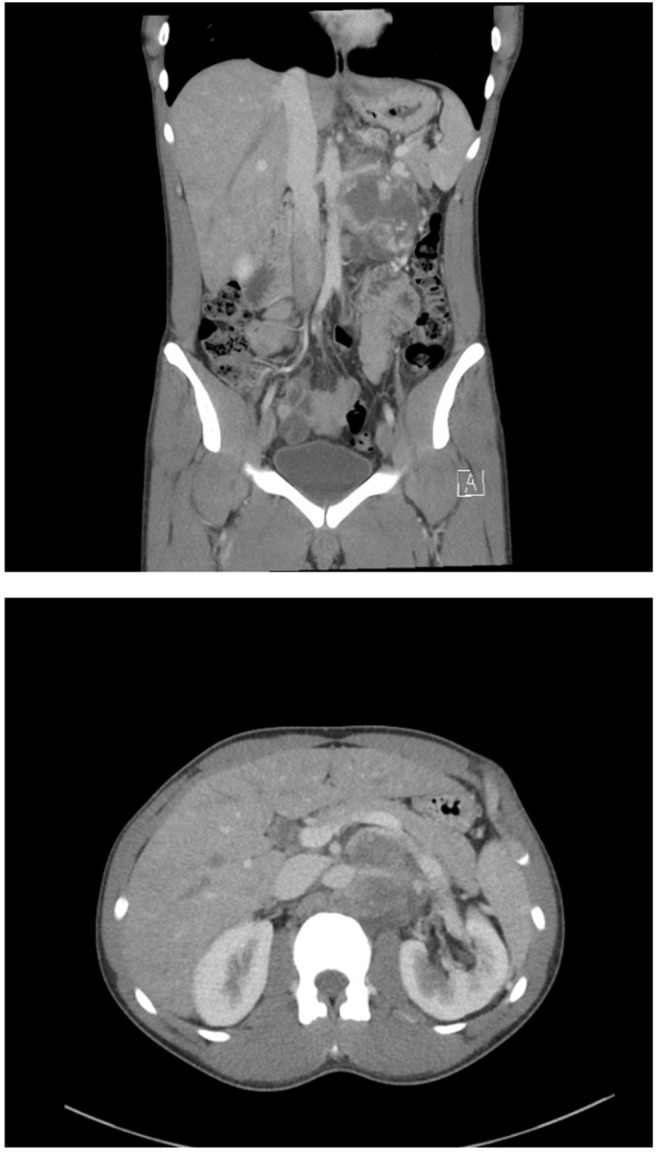

背景:腹膜后淋巴结清扫术(RPLND)在转移性睾丸癌的治疗管理中起着不可或缺的作用。作为一项大手术,RPLND有明显并发症的风险,特别是在化疗后(PC-RPLND)的情况下。我们评估了在澳大利亚一家三级医院引入RPLND作为一项新服务的安全性。方法:实施严格的方案,优先考虑适当的病例选择,多学科的外科专业知识和随时进入重症监护设施,以引入RPLND。前瞻性数据收集于2020年10月至2022年10月在墨尔本北部医院接受PC-RPLND的患者。主要终点和次要终点分别为术后30天Clavien-Dindo (CD)分级、并发症发生率和围手术期质量指标。结果:6例患者行双侧开模板PC-RPLND,平均年龄28.7±4.3岁。中位淋巴结计数为17 (IQR = 16),组织病理学检查均发现转移性生殖细胞瘤。中位住院时间为6天(IQR = 3),其中重症监护1天。不需要输血,也没有遇到30天的CD并发症。中位随访22个月(IQR = 21),无复发或明显的延迟并发症。结论:在严格的协议下,RPLND作为一项新服务安全地引入了我们的高等教育机构。围手术期质量终点与高容量国际中心相匹配。

Results: Six patients (mean age 28.7 ± 4.3 years) underwent bilateral template open PC-RPLND. Median node count was 17 (IQR = 16) with metastatic germ cell tumour identified in all patients on histopathology. Median length of stay was 6 days (IQR = 3) with 1 day in intensive care. No blood transfusions were required, and no 30-day CD complications were encountered. Median follow-up was 22 months (IQR = 21) with no recurrences or significant delayed complications.